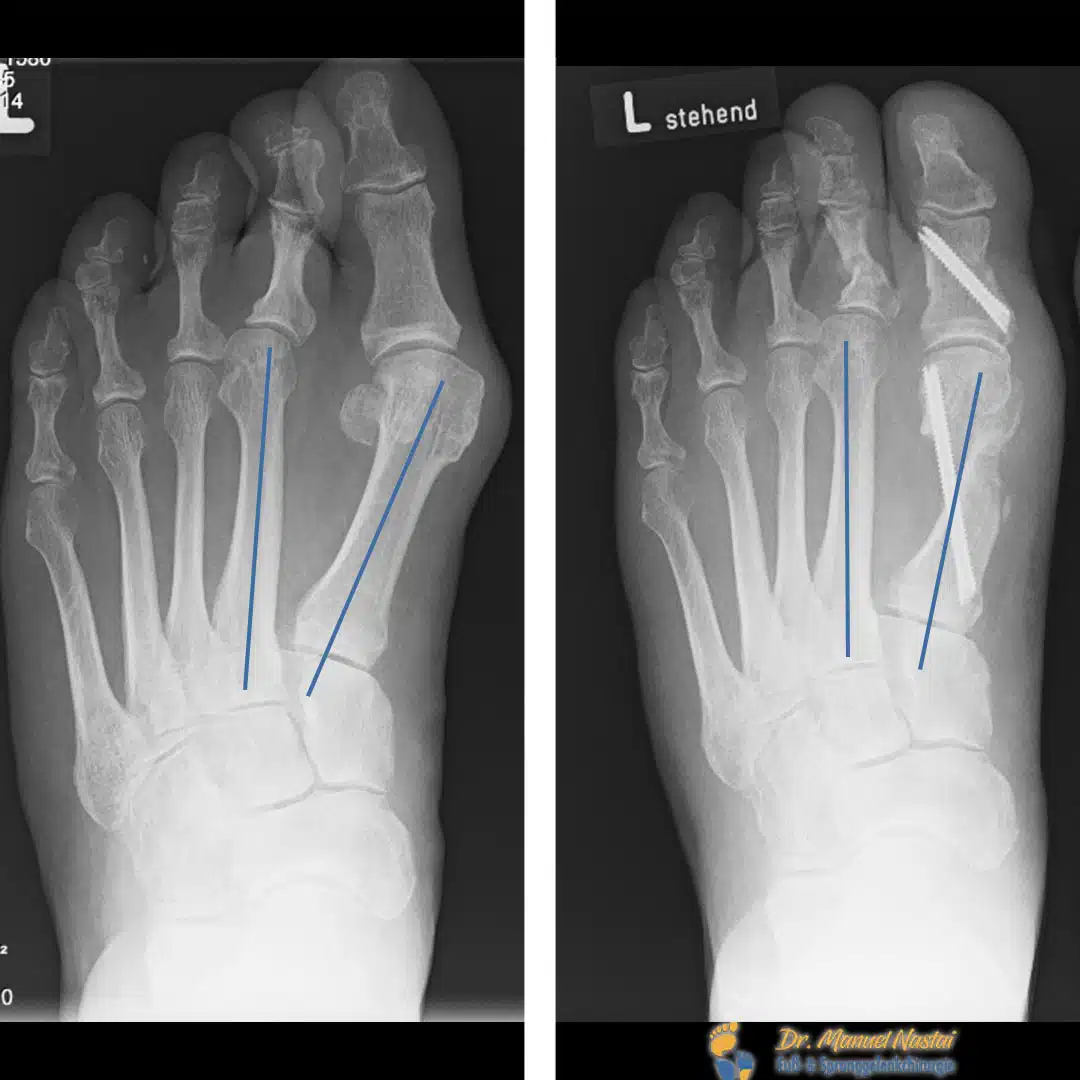

Präoperativ (links):

Dorsoplantar unter Belastung zeigt sich ein pathologisch vergrößerter Intermetatarsal-/IMR-1-Winkel (blaue Achsen) mit Spreizung von Strahl I–II. Das Köpfchen von MT I ist medial prominent; die Sesambeine sind deutlich nach lateral verlagert (orange). Zusätzlich besteht eine Z-förmige Achsabweichung des 2. Zehs („Zick-Zack-Zehe“).

Postoperativ (rechts):

Nach knöcherner Korrektur und schraubengesicherter Fixation ist der IMR-1/IMA deutlich verkleinert (blaue Achsen nahezu parallel), das MT-I-Köpfchen ist lateralisiert und rezentriert über den Sesambeinen (orange), das MTP-I erscheint kongruent. Der 2. Zeh steht wieder in gerader Achse. Die stabile Osteosynthese erlaubt die frühfunktionelle Vollbelastung im Spezialschuh.